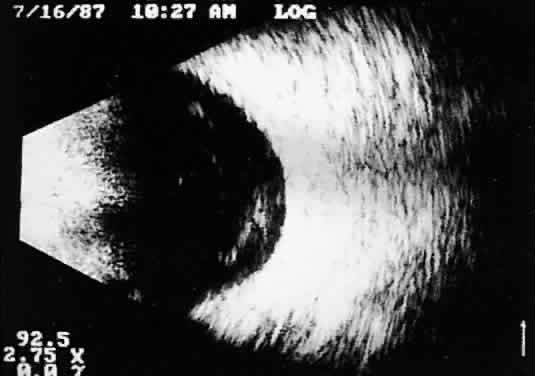

Real time refers to the display of motion or movement during B-scan imaging. This capability is one of the greatest advantages of B-scan. Differences in mobility of a variety of movable intraocular abnormalities can be easily detected. For example, the rapid movement of vitreous hemorrhage is usually easy to appreciate and differentiate from the slower, undulating movements of a recent, rhegmatogenous retinal detachment. On occasion, movement of intraocular structures can be used for detecting abnormalities that lie immediately behind vitreous opacification and may be seen only when the vitreous opacities are moved away from the ocular wall, set in motion by command voluntary movements of the patient's globe (Fig. 5). Gray scale refers to the variable gray tone of display screen echoes. Strong returning signals (echoes) appear white, whereas weaker reflections are seen as gray, the shade depending on echo strength. Examples of strong reflectors of sound include retinal tissue, sclera, and calcifications of any type (Fig. 6). Weaker echoes from clotted or clumped cells within the vitreous are usually easy to differentiate from the stronger reflectors of sound (Fig. 7). Grading of echo strength may be performed only when the examining ultrasound beam is perpendicular to the object of interest, ensuring the strongest possible reflections. However, in the world of ultrasound interpretation, there are many exception to the rules. Tissues that are usually mild reflectors of sound, such as hemorrhage, can at times appear quite strong, especially in complex or multiple pattern disorders, as frequently occur in severe ocular trauma. These apparent inconsistencies often cause misinterpretation by the novice. With experience obtained by multiple examinations, careful follow-up, and clinical correlation whenever possible, diagnostic acumen rapidly improves.

Fig. 5. Contact B-scans. A. Heavy formed vitreous hemorrhage obscuring choroidal mass. B. Voluntary movement of the globe causes the formed vitreous to shift, permitting easy detection of the ocular wall mass.